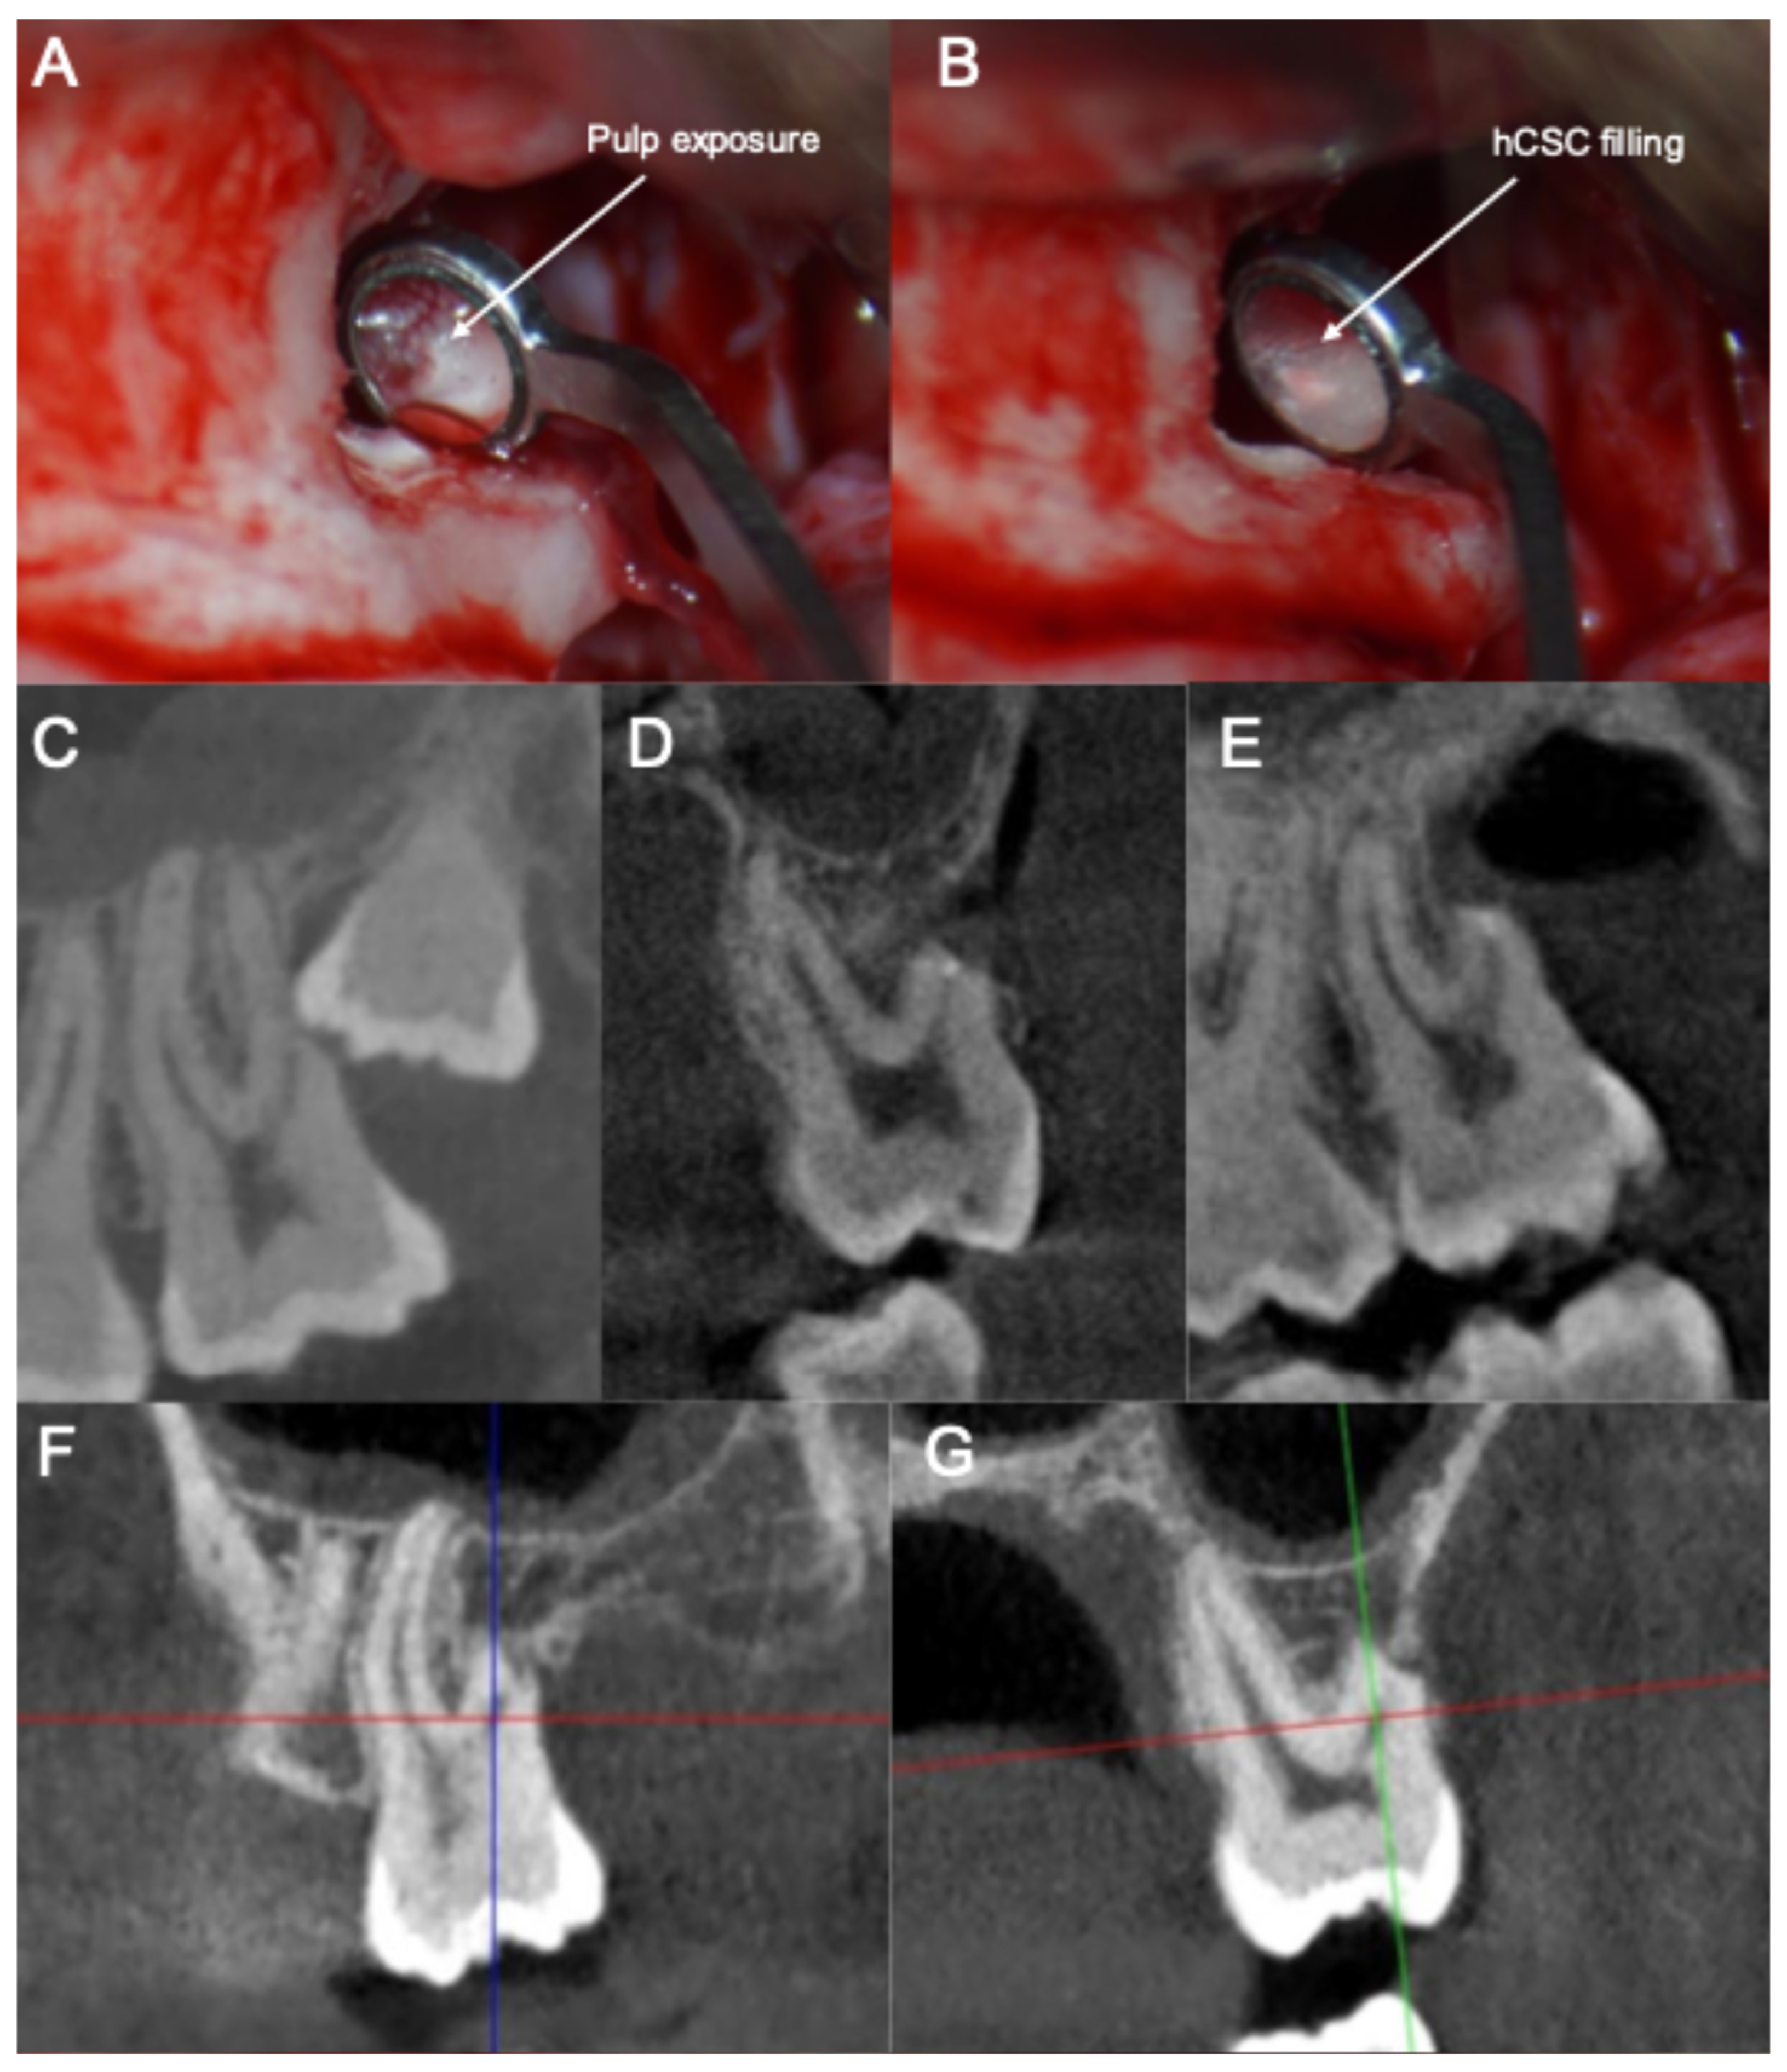

- (1)

- The smoothening of the ERR to allow for a clear visualization and access to the pulp exposure.

- (2)

- The creation of a retrograde cavity and partial pulpotomy of the pulp exposure.

- (3)

- The placement of a pulp capping agent in the cavity over the remaining vital pulp tissue.